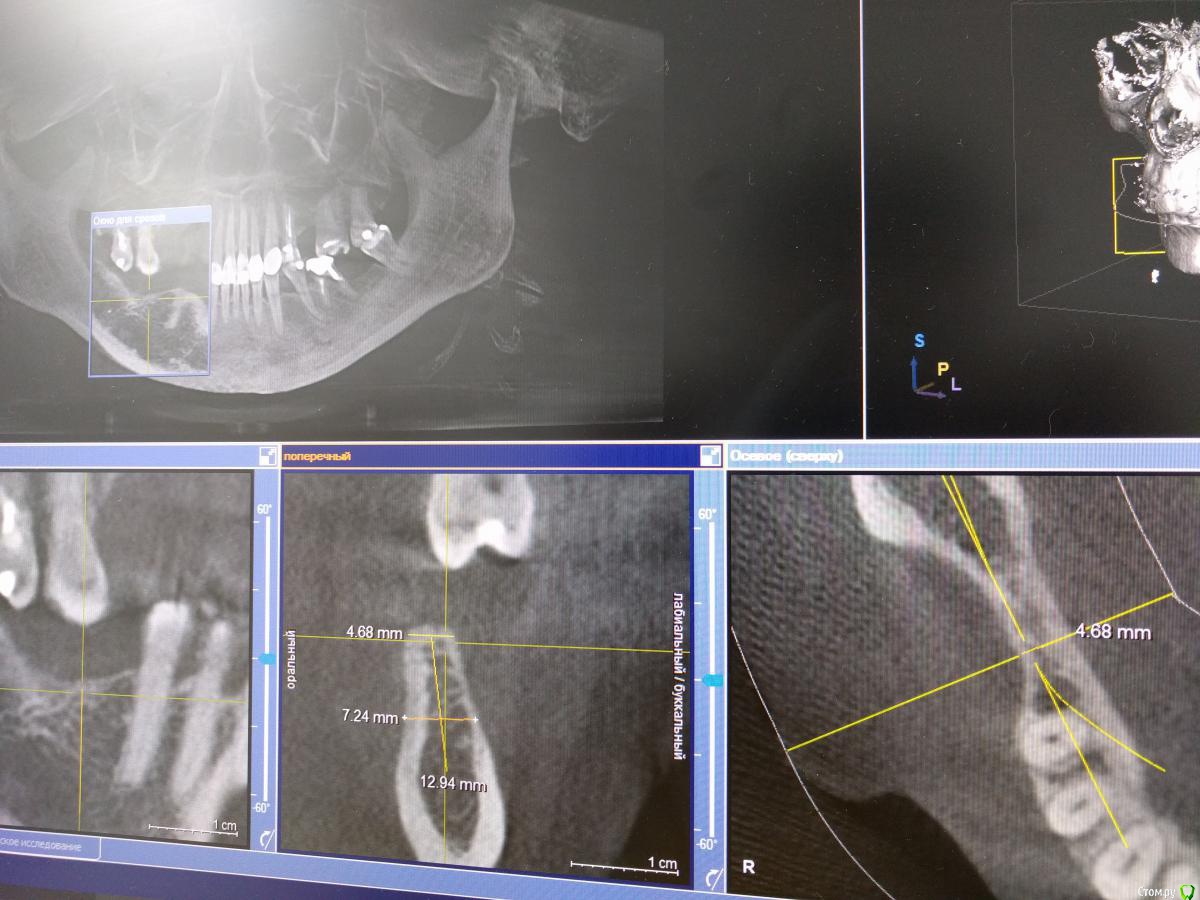

igorgergg Опубликовано 25 апреля, 2018 Поделиться Опубликовано 25 апреля, 2018 Всем привет, нужно экспертное мнение) Хочется сразу поставить имплпнты вместе с НКР. Прикладываю снимки КТ. По высоте все гуд, зафиксироваться проблемы не будет. Вопрос в том что половина импланта в правильном положении будет оголена. Естественно возле импланта уложу ауто стружку со скребка, а остальное забиваю церабоном с ауто 50/50. Нужен взгляд со стороны, спасибо. Ссылка на комментарий